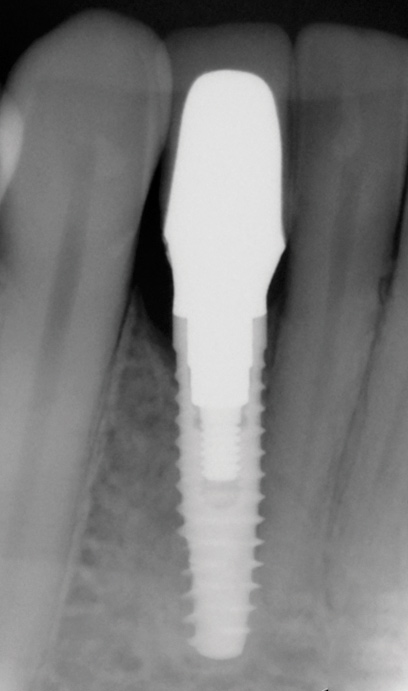

Fig 13. The final radiograph of the seated crown showing a healthy bone level around the implant.

Figure 13

Fig 17. Radiograph showed symmetrical infrabony defect affecting 50% of the implant surface.

Figure 17